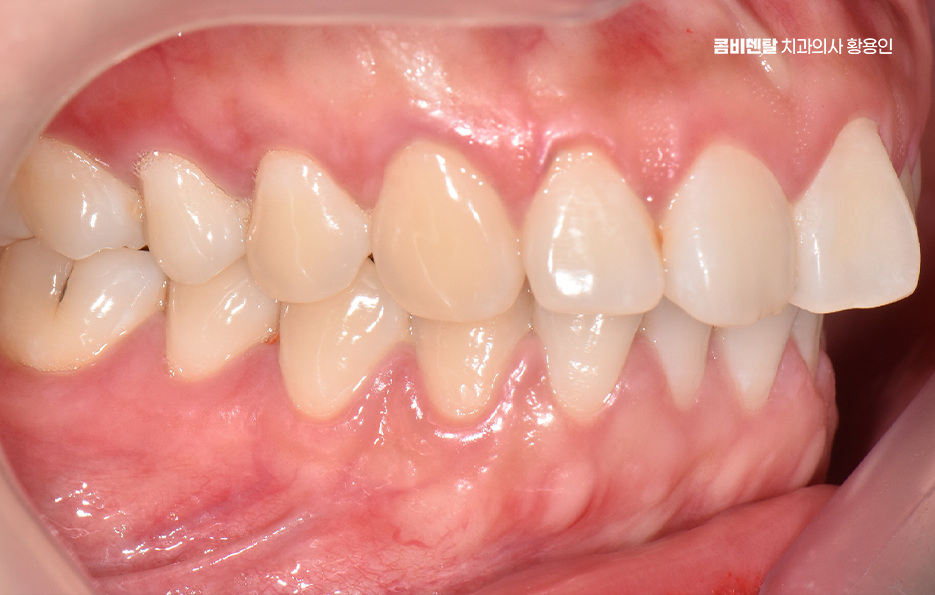

먼저 돌출입이라는 건 치아만 튀어나와 있는 경우도 있지만, 잇몸뼈 자체가 앞으로 튀어나와 있는 골격적인 돌출도 있는데 치아 돌출만 있는 경우는 치아 교정만으로도 비교적 간단하게 개선이 가능하지만 골격적인 돌출이 심한 경우에는 치아교정만으로는 한계가 있어서 수술교정을 병행해야 하는 경우도 있었어요.

하지만 대부분의 경우는 발치교정만으로도 충분히 개선이 가능하며 돌출입이 있을 때는 입술이 자연스럽게 다물어지지 않아서 턱 주변에 불필요한 힘이 들어가고, 표정이 어색해 보이기 쉬운데 이런 불균형을 치아 위치를 조절함으로써 완화시킬 수 있는 거예요.

돌출입 팔자주름 교정 치아를 어떻게 움직이느냐에 따라 얼굴 인상이 달라지는 것인데 돌출입 교정은 일반적으로 소구치 네 개를 발치한 후, 앞니를 뒤쪽으로 밀어넣고 악궁을 재배열하는 방식으로 진행되며 앞니가 뒤로 이동하고 자연스럽게 입술이 들어가게 되고, 입술 돌출도가 줄어들면서 얼굴이 전반적으로 부드럽고 조화로운 느낌으로 바뀔 수 있어요